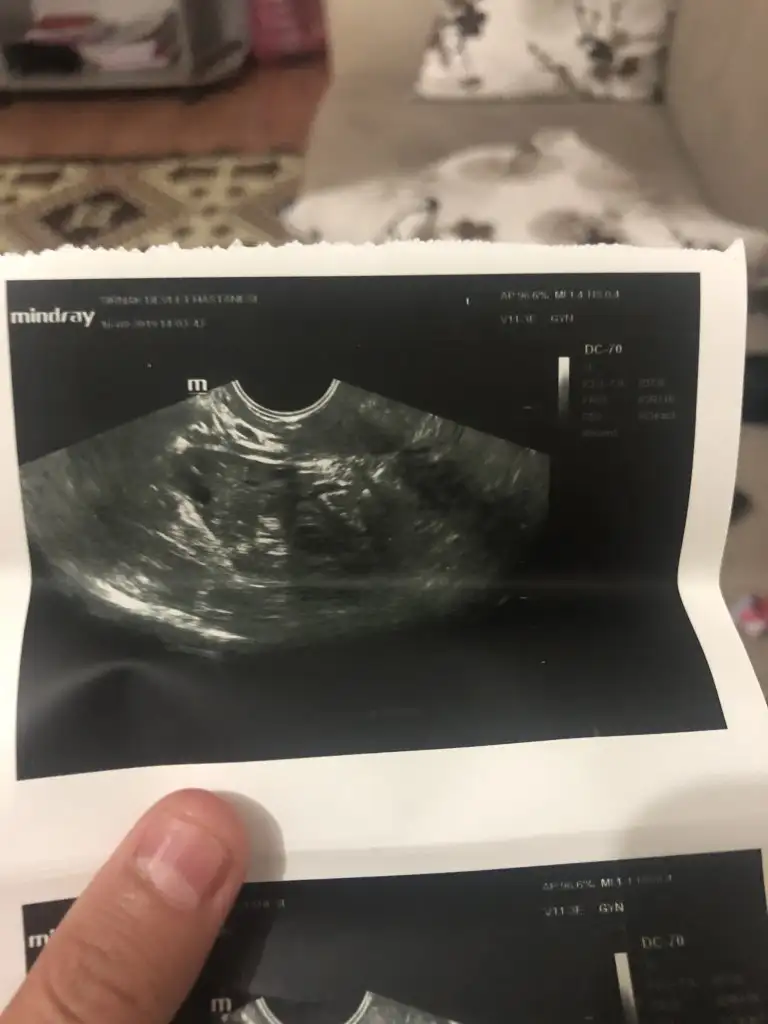

Ben bu ayın sonunda öğreneceğim hamile olup olmadığımı ama pek ümidim yok doktor olumlu bir şey demedi klomen kullandım 21. Günü hormon testine gdcem ultrason filmimde böyle kesin bişey demedide bilmiyorum yumurtanın birinde kist. Var diğerlri iyi dediEylülden umudunu kesip ekim ayında hayırlı hamilelik haberleri almak isteyen anne aday adayları beraber bekleyip birbirimize destek olalım ❤